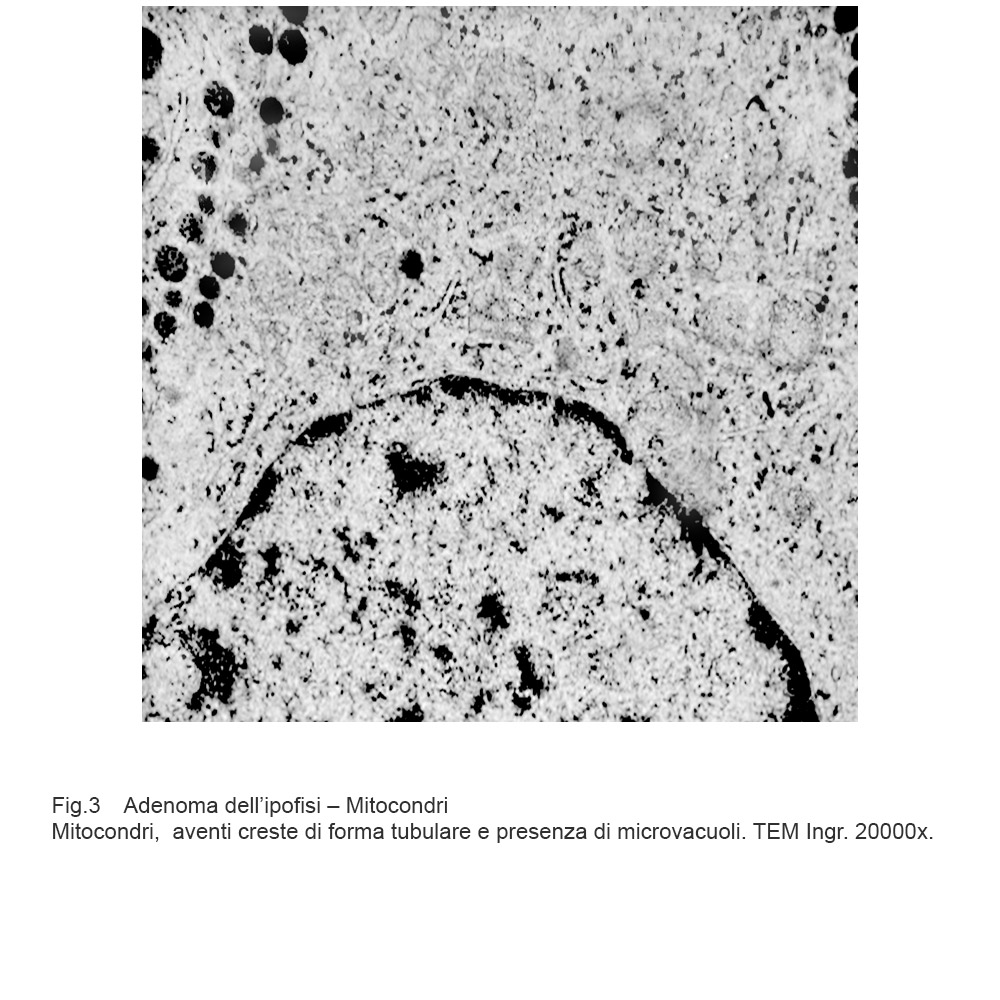

Cellule in attività secretiva le quali sono fornite di quote cospicue di mitocondri forniti di creste tubulari oppure di mitocondri rigonfi con creste in numero ridotto, spezzettate, disposte spazialmente in modo disordinato.

Fig.3  Fig.4

Fig.4

Mitocondri e R.E.: mitocondri con microvacuoli e depauperati di creste sono commisti a dilatazione micro-macrovacuolare del reticolo endoplasmico; alcuni di questi vacuoli sono occupati in modo parziale da materiale amorfo.